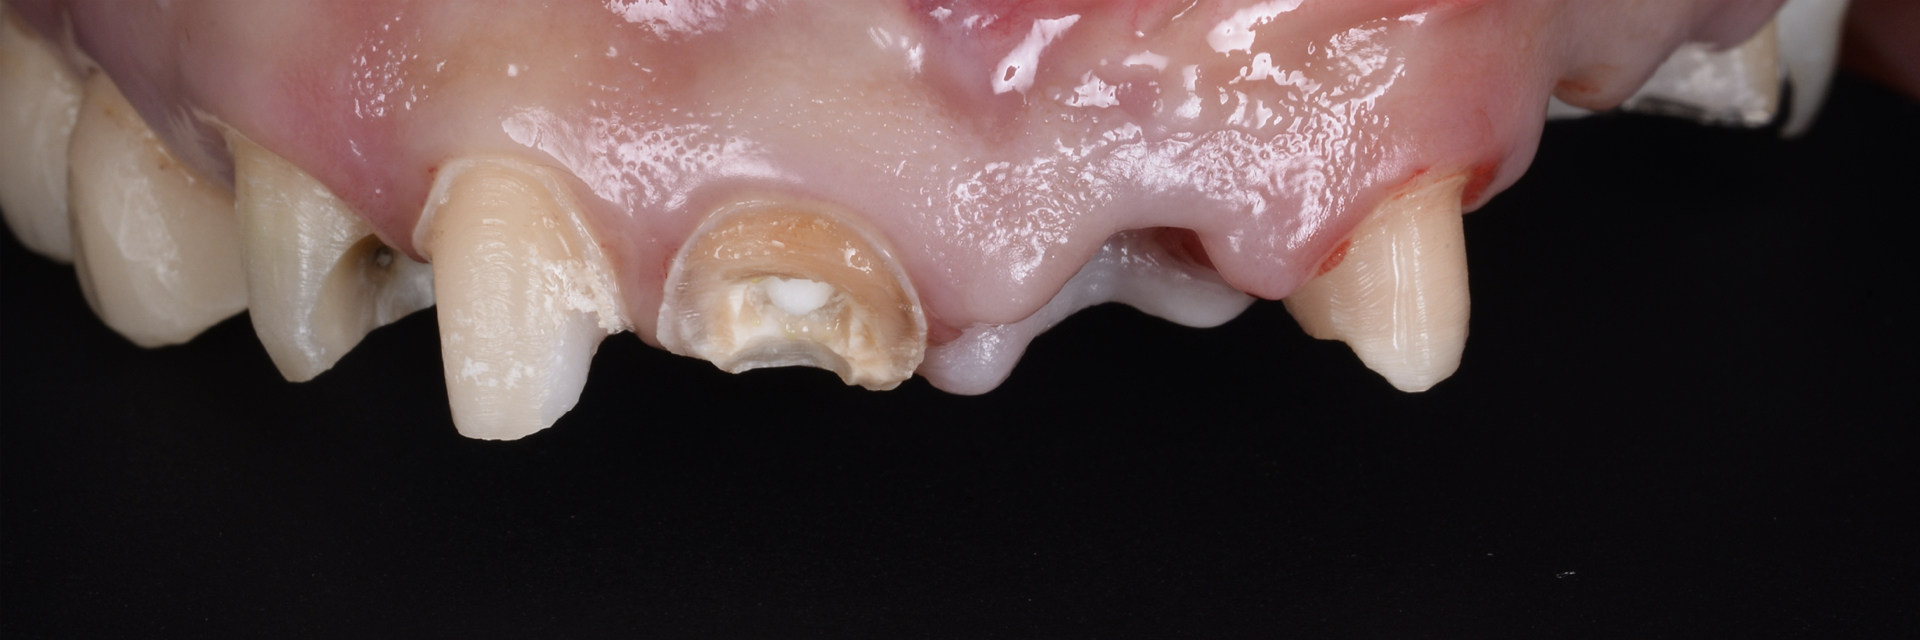

治療前

| 治療内容 | 5前歯をジルコニアベースのセラミッククラウンに置き換えました。 |